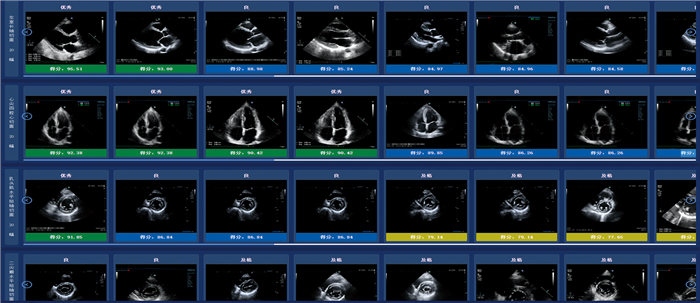

智能化超声医学质量控制平台(上海溯道智能科技有限公司)是国内首款专门针对超声医学质控问题研发的全方位智能化软件,率先实现了对腹部、颈部血管等部位的图像及报告智能化质控,已在部分三甲医院建立了超声实时质控会诊平台。在心脏超声方面,智能化超声医学质量控制平台经过对几十万例图像的学习、训练、建立模型,实现了对心脏6个标准切面的自动抓取以及对图像质量的智能评分(图 1)。PDCA循环管理法将质量管理分为计划(Plan)、执行(Do)、检查(Check)和处理(Act)4个阶段,形成周而复始的螺旋式上升改进的闭环管理过程,具有简单、逻辑性强、规模小和快速的特点,被广泛应用于医疗领域。我院超声科TTE质控小组利用智能化超声医学质量控制平台,结合PDCA循环管理法,对TTE中6个标准切面的图像质量进行质控管理,探讨两者在TTE标准切面质量控制中的应用价值,以期提高TTE标准切面获取的规范性和准确性。

图  1  智能化超声医学质量控制平台对经胸超声心动图标准切面的自动识别和智能评分

Fig.  1  Automatic identification and intelligent scoring of standard sections in transthoracic echocardiography by an intelligent ultrasound medical quality control platform